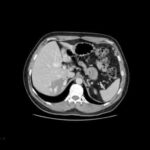

Primeiramente, precisamos saber o que é esse TEP. Na verdade, é um tromboembolismo pulmonar. Mas para que serve esse exame? Serve para detectar falhas de enchimento na região do coração, artérias e veias. É comum diagnosticarmos esse TEP através de outros meios, como cintilografia pulmonar, ressonância nuclear magnética e exames cardiológicos, como eletrocardiograma, ecocardiograma e exame de sangue. Mas, no nosso caso, vamos falar sobre a tomografia computadorizada de um protocolo TEP.

Ao iniciar a injeção do contraste, é dada a início ao exame. O roi irá acompanhar o contraste até chegar ao tronco pulmonar, onde faremos a varredura. Nesse momento, obtemos uma imagem do tronco pulmonar cheia de contraste.

No exame, podemos identificar estruturas como brônquios, esôfago, aorta ascendente e veia cava superior. Também podemos detectar falhas de enchimento e, caso existam, o médico poderá iniciar o tratamento específico.